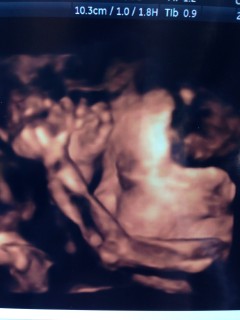

こっちを向いて目を開けて

口をぱくぱくしていました!

とても可愛い♪

ただ写真にするとちょっと怖いΣ(=ω= ;)笑